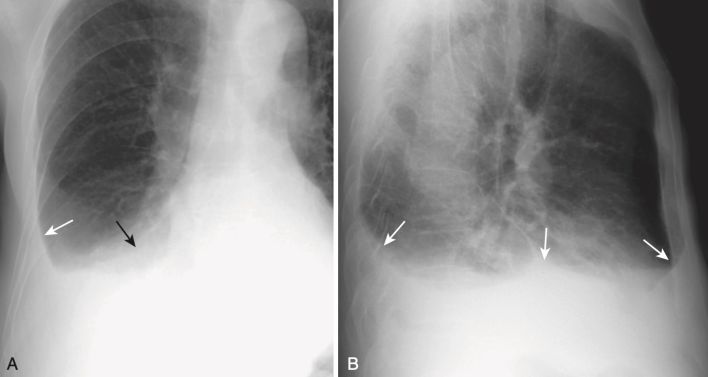

- Phim phổi ở tư thế nằm nghiêng

- Tác động của đặt tư thế bệnh nhân lên vị trí của dịch màng phổi có thể được sử dụng để tạo thuận lợi cho việc chẩn đoán bằng cách cho bệnh nhân nằm nghiêng về bên chứa dịch trong khi chụp chiếu lồng ngực bằng cách sử dụng chùm tia X hướng theo chiều ngang . Nếu bệnh nhân nằm nghiêng về bên phải, phim được gọi là phim phổi nằm nghiêng phải, và nếu bệnh nhân nằm nghiêng về bên trái, phim được gọi là phim phổi nằm nghiêng trái.

- Các phim ở tư thế nằm (nghiêng) có thể được sử dụng để:

- Khẳng định sự hiện diện của tràn dịch màng phổi.

- Xác định xem dịch màng phổi có chảy tự do trong khoang màng phổi hay không, một yếu tố quan trọng cần biết trước khi dẫn lưu dịch màng phổi.

- “Khám phá” một phần phổi bên dưới bị che lấp bởi tràn dịch.

- Nếu tràn dịch màng phổi có thể chảy tự do trong khoang màng phổi, dịch sẽ tạo ra một vùng hình dải đặc trưng với tăng đậm độ dọc theo bờ trong của lồng ngực ở bên thấp hơn (nghĩa là bên phải với phim nằm nghiêng phải và bên trái với phim nằm nghiêng trái). (Hình 9).

- Có thể dịch màng phổi không chảy tự do trong khoang màng phổi nếu có các kết dính cản trở sự lưu thông tự do của dịch (xem “Tràn dịch khu trú”).

- Các hình ảnh chụp ngực ở tư thế nằm (decubitus views) có thể phát hiện các tràn dịch lượng ít từ 15 đến 20 mL, nhưng chụp CT ngực đã thay thế phần lớn chụp tư thế nằm trong phát hiện một lượng rất nhỏ dịch màng phổi (Hình 10).